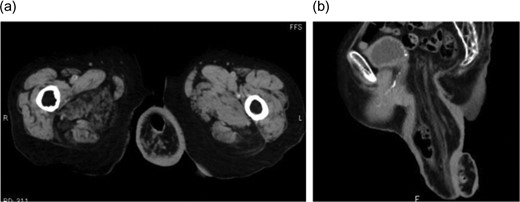

An 87-year-old woman presented to our hospital with a complaint of spontaneous massive rectal prolapse. She had been suffering from persistent rectal prolapse for over 5 years, and the length of the prolapsed rectum continued increasing. At the time of presentation, the prolapsed rectum was over 20 cm long and severely edematous (Fig. 1); therefore, it was completely irreducible. She had no apparent past medical history, and no other remarkable finding was present on physical examination. Her QOL was severely impaired since she was unable to even sit normally. Pelvic computed tomography showed full-thickness prolapse of the redundant rectosigmoid colon from the anus (Fig. 2); thus, she was diagnosed with Tuttle II type complete rectal prolapse.

Pelvic computed tomography image. Full-thickness prolapse of redundant rectosigmoid colon from the anus is observed. (a) Axial section and (b) sagittal section.